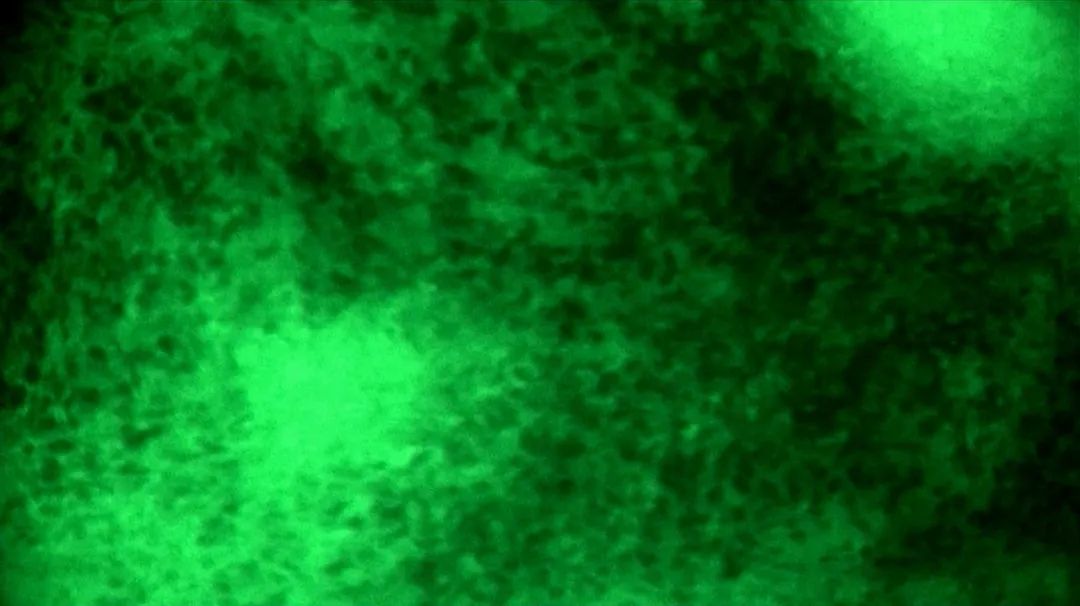

醫(yī)生在術(shù)中導(dǎo)航及電生理監(jiān)測下將腫瘤病灶主體切除后,使用EndoSCell?對瘤腔進(jìn)行了近10分鐘滑動式掃描檢查,在瘤腔側(cè)緣發(fā)現(xiàn)了一處細(xì)胞核呈明顯異型、分布密集且不規(guī)則的組織,判斷為殘留病灶并進(jìn)行擴(kuò)切。隨后再次使用EndoSCell?探查,圖像顯示整個瘤腔均為正常細(xì)胞形態(tài),由此判定切緣陰性,可進(jìn)入關(guān)顱等后續(xù)步驟。

腫瘤細(xì)胞與正常細(xì)胞的ES圖像對比

陽性:細(xì)胞核異型、密集、分布不均勻

陰性:細(xì)胞核形態(tài)正常、分布均勻